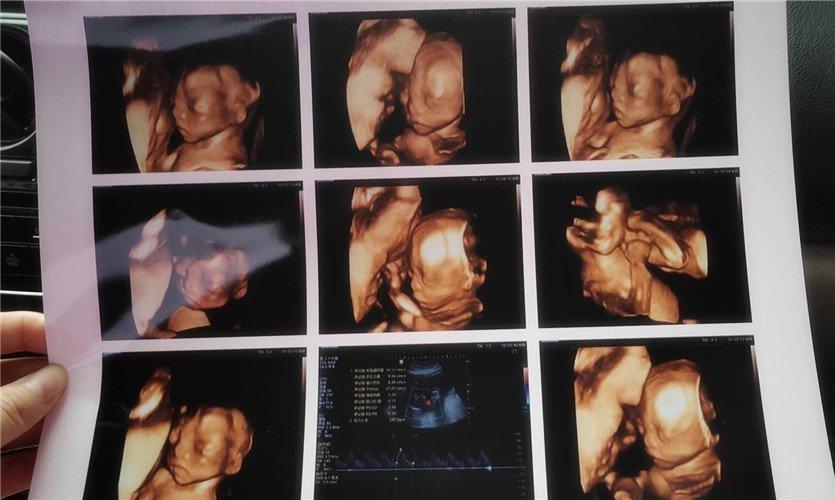

四維彩超是一種先進(jìn)的醫(yī)學(xué)影像技術(shù),通過實(shí)時(shí)觀察胎兒在母體內(nèi)的活動(dòng)情況,為醫(yī)生提供了豐富的診斷信息,在四維彩超下,我們可以清晰地觀察到胎兒的蛋蛋(睪丸)的形態(tài)、位置和大小等特征,胎兒蛋蛋是男性生殖系統(tǒng)的重要組成部分,對于胎兒的生長發(fā)育具有重要意義。

在四維彩超下,胎兒蛋蛋呈現(xiàn)出特定的形態(tài)和外觀,通常情況下,胎兒蛋蛋呈現(xiàn)出圓形或橢圓形,表面光滑,內(nèi)部回聲均勻,隨著胎兒的發(fā)育,蛋蛋會逐漸增大,并呈現(xiàn)出明顯的性別特征,醫(yī)生可以通過四維彩超技術(shù),對胎兒蛋蛋的大小、形態(tài)和位置進(jìn)行評估,以判斷胎兒生殖系統(tǒng)的健康狀況。

胎兒蛋蛋的發(fā)育是一個(gè)復(fù)雜的過程,受到多種因素的影響,在胎兒發(fā)育的早期階段,蛋蛋位于腹腔內(nèi),隨著胎兒的生長發(fā)育,蛋蛋逐漸下降至陰囊,這個(gè)過程受到激素、遺傳和環(huán)境等多種因素的影響,在四維彩超的觀測下,我們可以實(shí)時(shí)了解胎兒蛋蛋的發(fā)育過程,及時(shí)發(fā)現(xiàn)異常情況并采取相應(yīng)的治療措施。

四維彩超技術(shù)在評估胎兒蛋蛋發(fā)育方面具有重要意義,通過四維彩超,醫(yī)生可以實(shí)時(shí)觀察胎兒蛋蛋的形態(tài)、位置和大小等特征,了解胎兒生殖系統(tǒng)的發(fā)育情況,四維彩超還可以幫助醫(yī)生發(fā)現(xiàn)可能的異常情況,如睪丸未降、睪丸囊腫等,為及時(shí)采取治療措施提供依據(jù)。